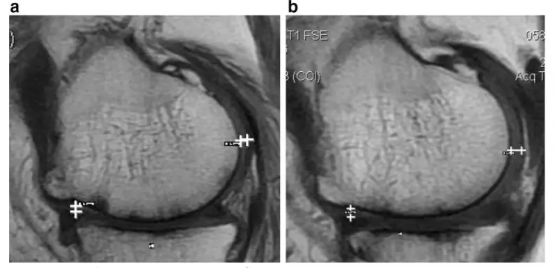

評估指標:WOMAC 評分丨MRI

研究結果:經過 2 年的治療,WOMAC 評分也有所改善。6 分鐘內的步行距離也顯著增加。60% 的患者軟骨體積增加。

注:如上圖所示,左圖為治療前,右圖為治療后,白色“+”處示意軟骨增厚。